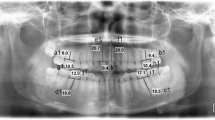

One dry skull from a young adult cadaver with a complete set of teeth was used in this study. The skull was obtained more than 15 years ago, and it is impossible to identify the donor. Five small bone chips (weight range 7–15 mg, thickness 1 mm), which were obtained from cortical bone of the cervical spines of dairy cows, were used to simulate bone changes. The weight of each bone chip is given in Table 1. These bone chips were confirmed to detect bony changes by subtraction analysis with film. Each bone chip was placed on the buccal surface of alveolar bone around the alveolar crest of the maxillary premolar or molar teeth of the dry skull. Figure 1 shows an example of the dry skull with a placed bone chip. In this sample image, the bone chip was placed on the facial alveolar bone surface of the interproximal area between the second premolar and the first molar.

Exposure was set at 60 kV and 7 mA (HD-70 X-ray generator; Asahi Roentgen, Kyoto, Japan). The CCD sensor was set behind the upper molar and premolar teeth. The focus-to-sensor distance was set at 25 cm. The presence of soft tissue was simulated by placing a 1-cm-thick piece of a soft-tissue equivalent material (Tough Water Phantom; Kyoto Kagaku, Kyoto, Japan) in the appropriate place. Figure 2 shows the exposure geometry.